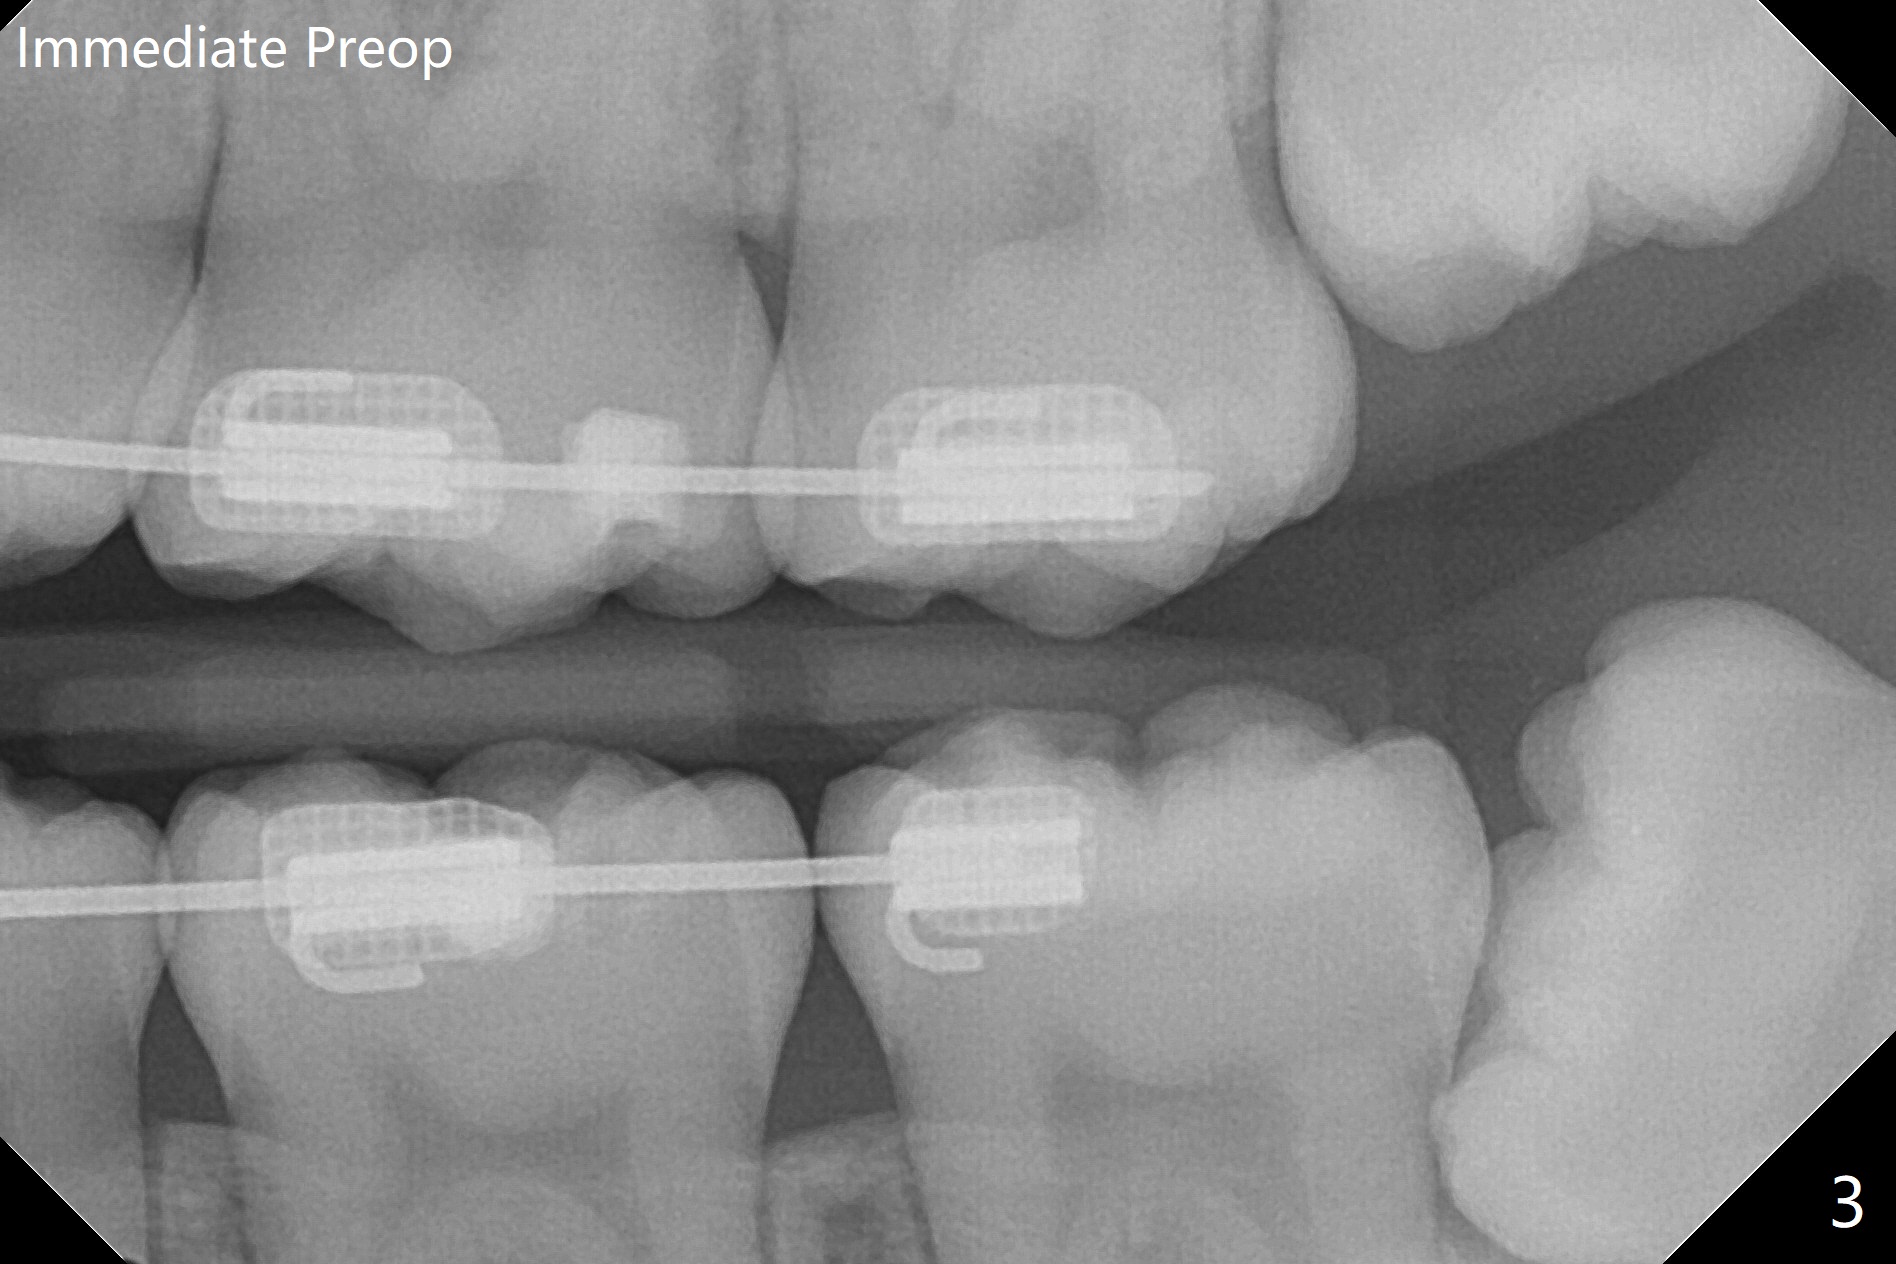

17岁女孩3年前拍摄全景片后拔除4个第一双尖牙(图一),在别的诊所进行矫正(图二,三),在局麻下拔除4个智齿,由于去骨,显得外斜嵴缺失(图四:箭头),放置胶原塞(防止干槽症),4-0含铬羊肠线缝合,预计外斜嵴6-12月能修复。